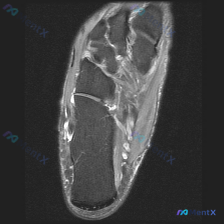

足部MRI看到积液被误判为软组织?这个距下关节病例的鉴别思路值得复盘

这是一份足部MRI T2序列冠状位图像,切面覆盖足后部到中足的解剖结构,核心观察结果如下:

- 距下关节区域:关节间隙可见明确线性高信号,符合关节积液表现;关节边缘可见骨质增生(骨赘),局部轮廓不规则突起

- 周围软组织与肌腱:内侧肌腱形态信号基本正常,无明显腱鞘异常高信号;软组织层面未见弥漫性水肿或占位性病变

- 骨骼信号:距骨、跟骨骨髓信号为中等强度,无明显骨髓水肿高信号或骨折线,骨皮质轮廓完整